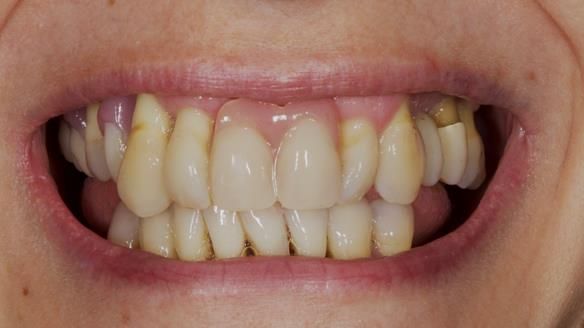

She had previously suffered from generalised periodontitis – stage IV, grade C, currently stable, with reduced attachment across the upper arch.

By the time she came to me, her periodontal condition was stable — but the aesthetics in the upper jaw were very poor.

Dr Syed Abad — my colleague and a Specialist in Periodontics — had successfully stabilised her gum health.

We provided her with an immediate upper denture (Mk 1), followed by a definitive metal-based upper denture (Mk 2). A lower removable partial denture was discussed, to be made only if needed once the upper treatment was complete. However, at review, this wasn’t necessary — Adnana had excellent neuromuscular control and function, even with a shortened dental arch (SDA).